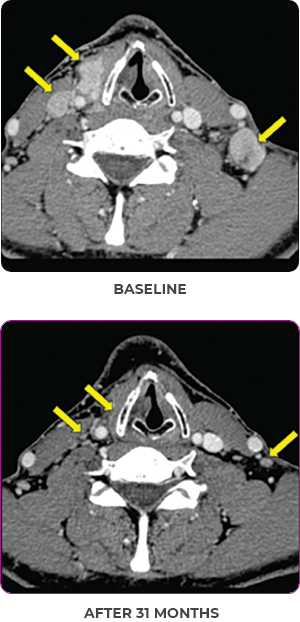

PATIENT CASE:

METASTATIC, RAIa-REFRACTORY,

PAPILLARY THYROID CANCER1,2

- 33-year-old male

- Progression on RAI and first line systemic therapy

- PRa after 2 cycles of VITRAKVI® (larotrectinib)

- Confirmed partial response on VITRAKVI lasting 55 cycles

Clinical presentation1

- Initially diagnosed at age 27

- Bulky disease in neck and thoracic involvement; metastatic, RAI-refractory papillary thyroid cancer

Response to VITRAKVI1,2

- Confirmed partial response (92.6% reduction in target lesions)

- Treatment continued for 55 cycles

- VITRAKVI was well tolerated; patient did not have to discontinue due to AEa

- No treatment interruptions or dose reductions

Response in primary and metastatic lesions1

Images courtesy of Dr Steven Waguespack.